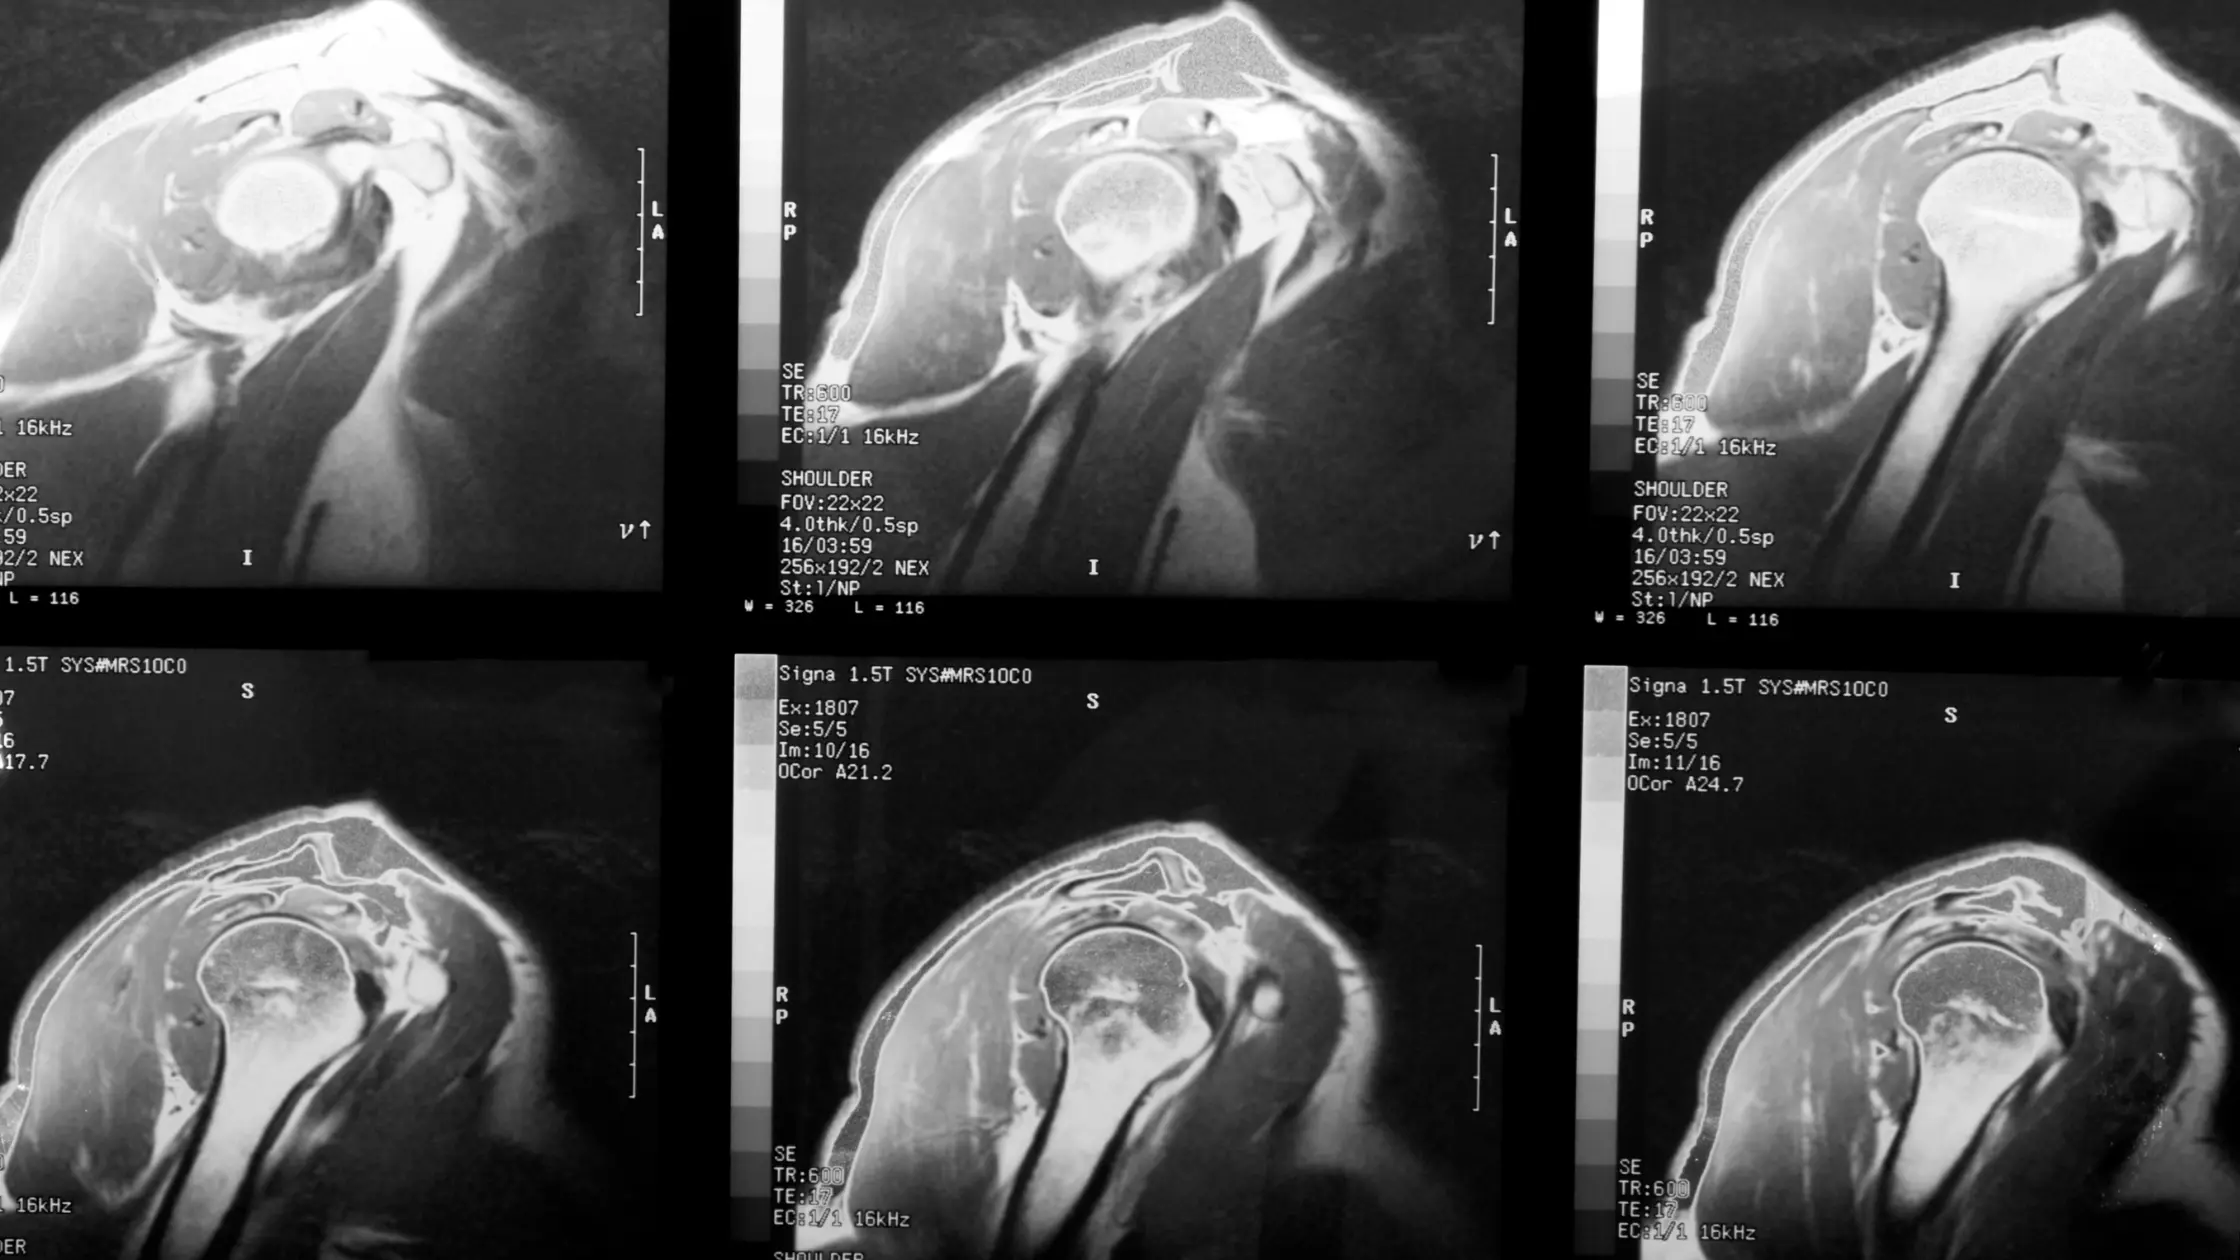

Coafa rotatorilor - Simptome, cauze și tratament al lez...

Simptome, cauze și metode de tratament recomandateLeziunea coafei rotatorilor este un...